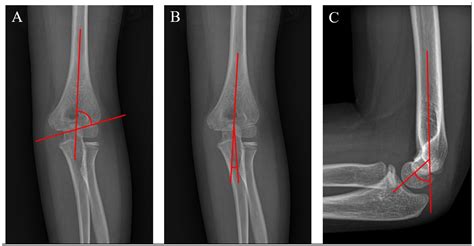

Diagnosing a supracondylar humerus fracture involves a thorough physical examination and imaging studies. The healthcare provider will assess the elbow for signs of injury, such as swelling, deformity, and tenderness. Imaging studies, such as X-rays, are crucial for confirming the diagnosis and determining the type and severity of the fracture.

X-rays are typically taken from multiple angles to provide a comprehensive view of the fracture. In some cases, additional imaging studies, such as a CT scan or MRI, may be necessary to assess the extent of the injury and plan the appropriate treatment.

Supracondylar humerus fractures are classified based on the direction of the fracture line and the displacement of the bone fragments. The most commonly used classification system is the Gartland classification, which includes three types:

Type Description

Type I Non-displaced fracture with minimal angulation

Type II Displaced fracture with posterior angulation of the distal fragment

Type III Completely displaced fracture with no cortical contact between the fragments

Understanding the classification of the fracture is essential for determining the appropriate treatment plan.